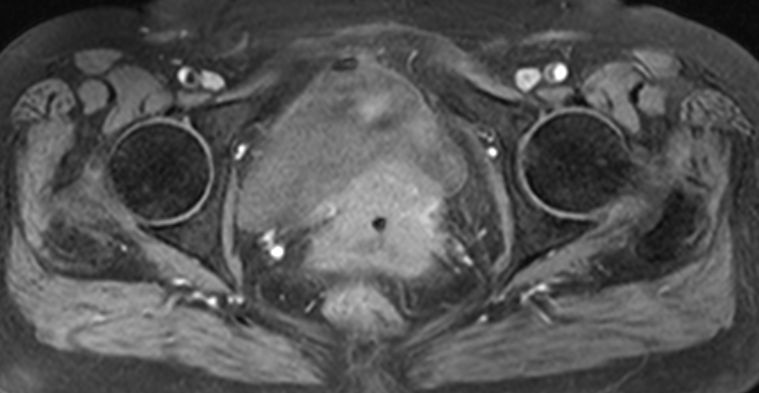

| MRT | 71jährige Frau, die wegen Uterus-Totalprolaps eingeliefert wurde. Der Uterus wurde reponiert und zeigte einen 5cm großen Zervixtumor. | |||